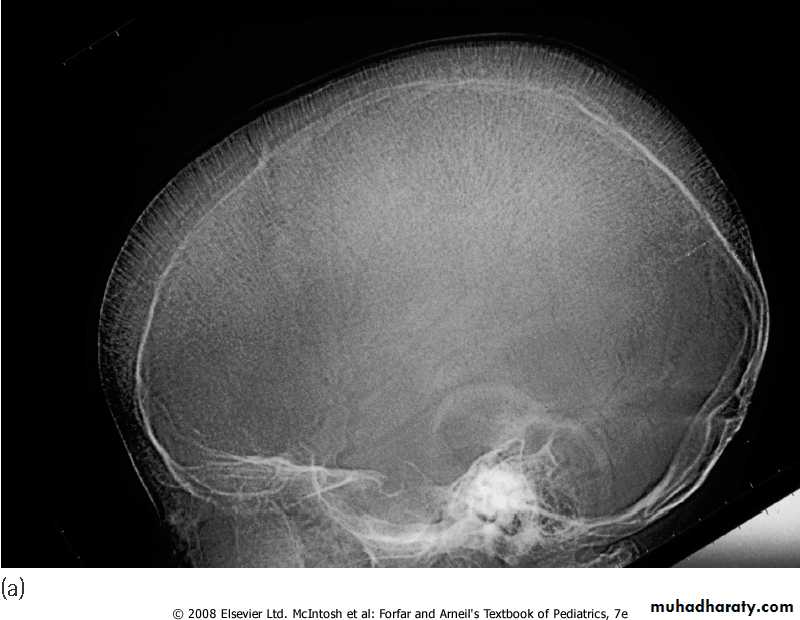

3-On Hb electrophoresis, Hb A is either markedly decreased or totally absent. Of the total Hb concentration, 30% to 90% is Hb F.4-BM hyperplasia is seen in bone XR.

5-Elevated S.ferretin & transferrin saturation.Skull X-ray showing ‘hair on end’ appearance caused by marrow hyperplasia and expansion